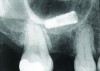

Implant related complications may be classified as minor, intermediate, major reversible/nonreversible, or major nonreversible. For example, a simple complication like a fractured abutment screw is usually considered a minor complication. It usually can be corrected with minimal cost, time, pain, and inconvenience. Treatment may be more involved for an intermediate complication such as a fractured implant (Figure 1). Up the severity scale are major complications, such as when an implant migrates into the sinus2 (Figure 2), or is exposed by mucosa and bone loss and visible to the patient a year after restoration (Figure 3 and Figure 4). Major complications may cause irreversible damage and/or require multiple procedures to try to make the patient “whole,” adding cost, time, pain, and surgeries (Figure 5 and Figure 6), and the patient may or may not receive the original restoration.

An implant that migrated into the sinus may be considered a major reversible complication.

Figure 2